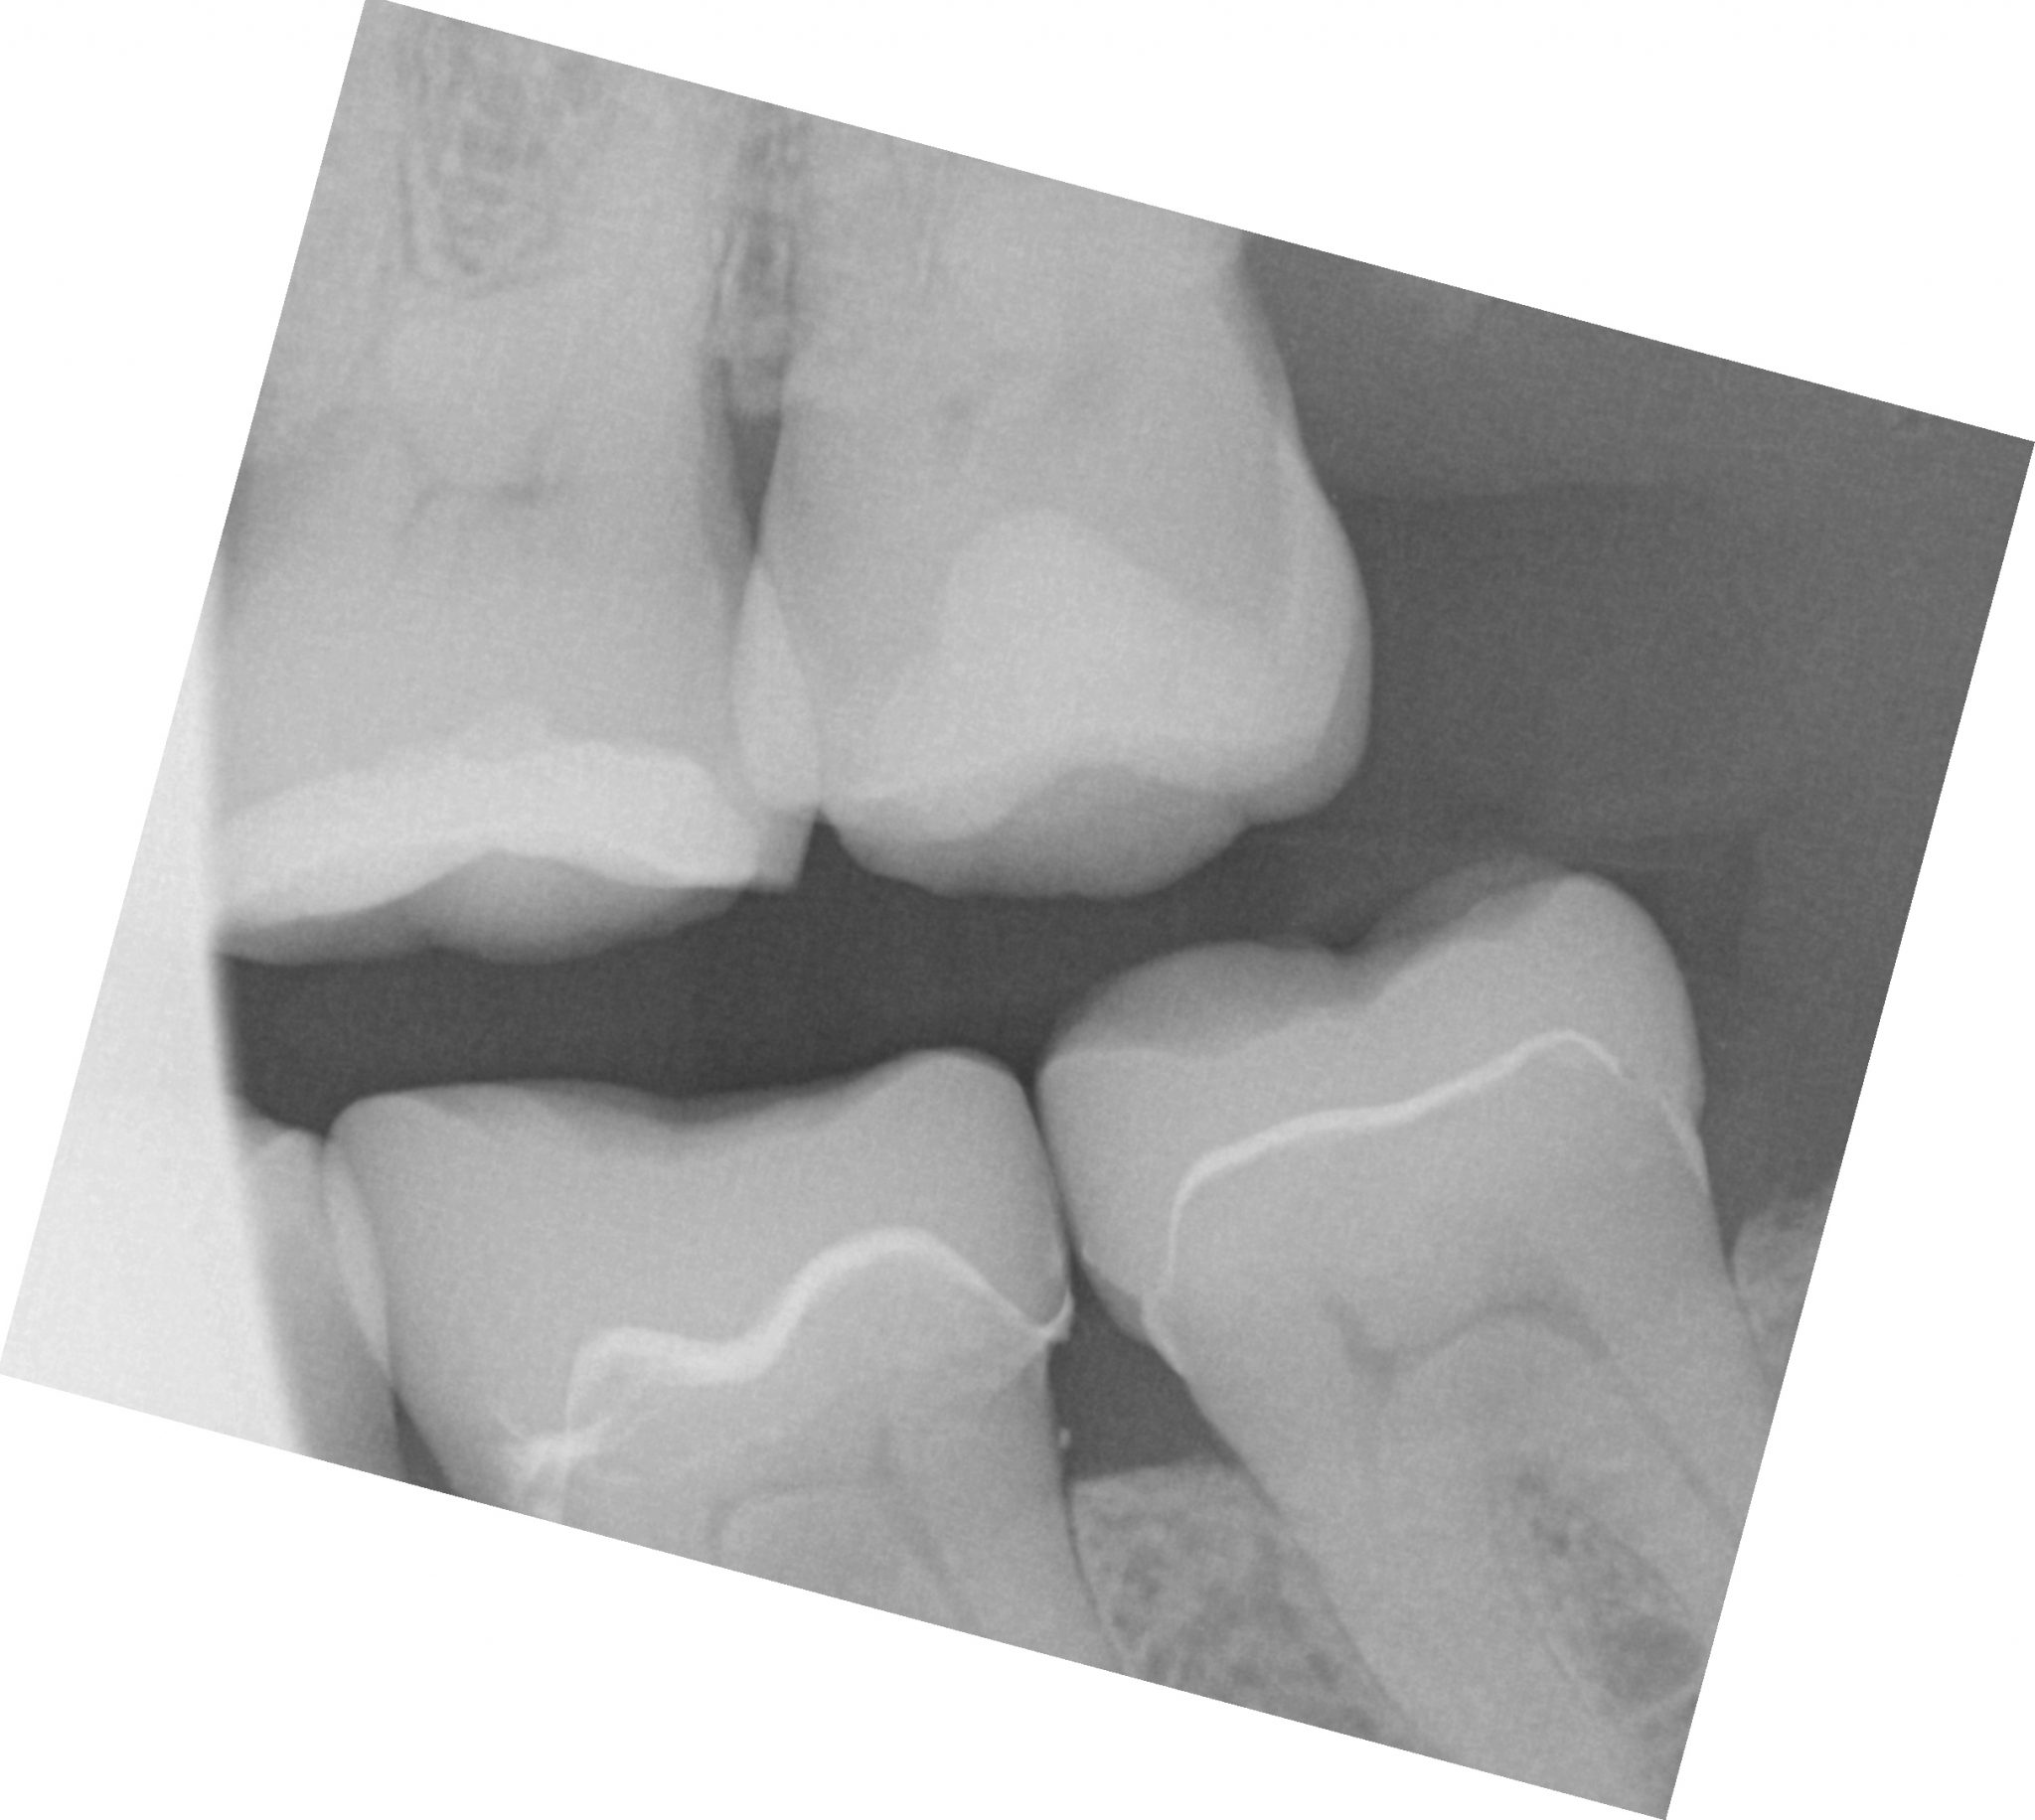

For the second molar, we will take advantage of the anesthesia time and capture the first bite, the opposing, the pre-existing situation and then crop out the preparation area digitally. Once the tooth is prepared, we will check for proper reduction. We will then take the second bite to verify the vertical dimension has not changed.